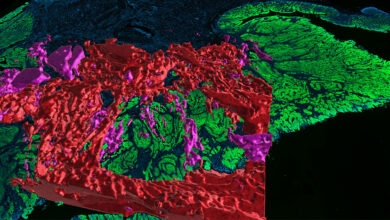

Researchers are building detailed maps of colorectal cancer to better understand the dynamics of the disease

A 3D reconstruction of colorectal cancer revealed that what was once thought to be 2D mucin pools with clusters of…